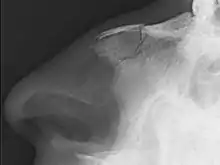

| Plain X-ray showing a nasal fracture | |

The most common causes include assault, trauma during sports, falls, and motor vehicle collisions.[1] Diagnosis is typically based on the signs and symptoms and may occasionally be confirmed by plain X-ray.[1]

Nasal fractures are usually identified visually and through physical examination.[1] In addition, relevant questions to ask the patient include whether there is a noticeable cosmetic deformity and whether the patient has difficulty breathing through the nose after the injury. Medical imaging is generally not recommended.[1][3] A priority is to distinguish simple fractures limited to the nasal bones (Type 1) from fractures that also involve other facial bones and/or the nasal septum (Types 2 and 3). In simple Type 1 fractures X-Rays supply surprisingly little information beyond clinical examination. However, diagnosis may be confirmed with X-rays or CT scans, and these are required if other facial injuries are suspected.[3]